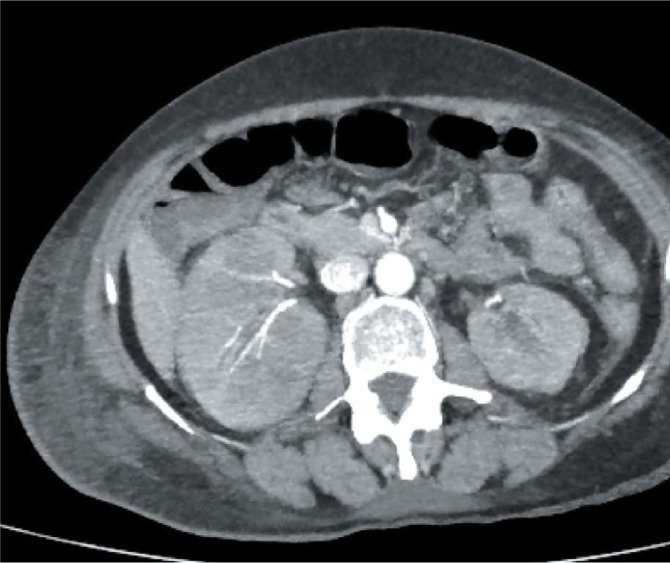

Case description: We report a case of a 39-year-old premenopausal female with relapsed HER2-positive breast cancer complicated by an invasive fungal infection. The patient initially presented with a 5 × 5 cm right breast lump, which was diagnosed as invasive ductal carcinoma, HER2-positive estrogen and progesterone receptor negative. Despite receiving chemotherapy with doxorubicin, cyclophosphamide, paclitaxel in the neoadjuvant setting and breast conservation surgery, the patient experienced disease recurrence. She was then treated with modified radical mastectomy followed by adjuvant chemotherapy TCH (trastuzumab, carboplatin, and docetaxel) six cycles. After three cycles, she developed high-grade fevers, renal impairment, and altered mental status. Imaging initially suggested ongoing infective vs metastatic process in bilateral renal and CNS parenchyma, so biopsy was performed from brain that revealed Aspergillus flavus infection. Treatment was adjusted to include antifungal therapy with voriconazole, and the patient's condition improved.